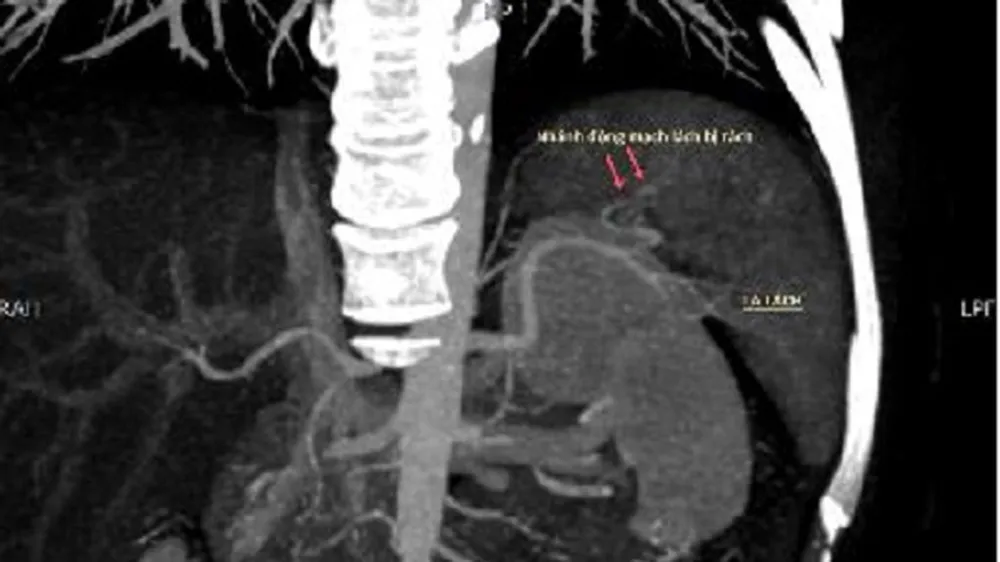

Bác sĩ dùng một ống thông nhỏ đường kính 1-2mm, luồn từ vùng bẹn phải vào động mạch đùi, đưa lên động mạch chủ vào động mạch lách. Từ động mạch lách, bác sĩ bơm thuốc cản quang chụp toàn bộ hệ động mạch của lách, tìm đến động mạch bị vỡ gây chảy máu ổ bụng.

Sau khi xác định được mạch máu bị tổn thương, thuốc tắc mạch sẽ được bơm vào động mạch bị vỡ để cầm máu và giúp lành vết thương. Hiện tại sức khỏe bệnh nhân đã qua cơn nguy kịch.